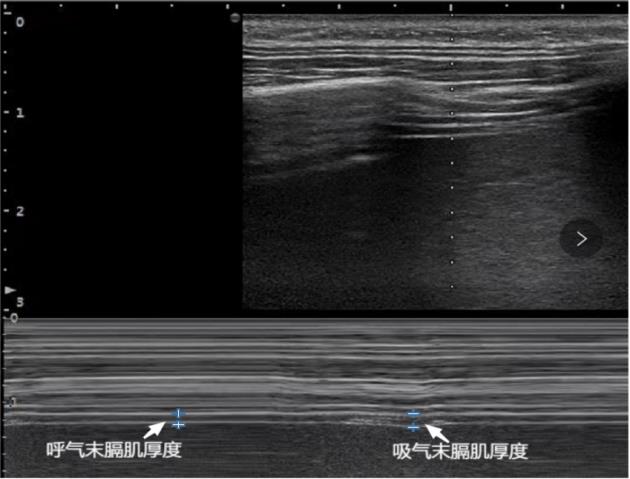

目的 研究在小儿腹腔镜腹股沟疝手术麻醉过程中,使用膈肌超声指导喉罩拔除时机的可行性和安全性。 方法 选取腹腔镜腹股沟疝修补手术患儿140例,随机将患儿分为膈肌超声指导拔除喉罩组(D组)和清醒拔除喉罩组(A组),两组患儿分别按照不同方式指导喉罩的拔除时机,比较两组患儿喉罩拔除过程中及拔除后出现咳嗽、拔除困难、喉痉挛、支气管痉挛、咽痛等呼吸不良事件的发生率,分析比较两组患儿外周血氧饱和度下降的发生率及处理方式。 结果 D组患儿拔除困难和喉痉挛的发生率均低于A组患儿,差异有统计学意义(P < 0.05),D组患儿发生呼吸不良事件的病例数少于A组患儿,差异有统计学意义(P < 0.05)。D组患儿拔除喉罩后血氧饱和度下降的发生率低于A组患儿,差异有统计学意义(P < 0.05)。D组患儿手术结束至拔除喉罩时间及Steward苏醒评分达4分时间均短于A组患儿,差异有统计学意义(P < 0.05)。 结论 在小儿腹腔镜腹股沟疝手术麻醉苏醒过程中,采用超声监测膈肌厚度变化率的方式可以更好地指导拔除喉罩,安全性更高。

Objective To investigate the feasibility and safety of using diaphragmatic ultrasound to guide timing of laryngeal mask extraction during anaesthesia for laparoscopic inguinal hernia surgery in children. Methods A total of 140 children undergoing laparoscopic inguinal hernia repair surgery were selected, and the children were randomly divided into two groups: the group with laryngeal mask extraction guided by diaphragmatic ultrasound (Group D) and the group with laryngeal mask extraction guided by awake (group A). The two groups were instructed on the timing of laryngeal mask extraction according to different ways, and the incidence of adverse events, such as difficulty in pulling out, cough, laryngospasm, bronchospasm, and pharyngeal pain, were compared between the two groups during and after the extraction, the analysis compared the incidence and management of peripheral oxygen desaturation between the two groups. Results The rates of difficulty in pullout and laryngospasm in group D were both lower than those in group A, and the number of cases of adverse events in group D was lower than that in group A, the difference was statistically significant. The incidence of oxygen desaturation after removal of the laryngeal mask was lower in group D than in group A, and the difference was statistically significant.The time from the end of surgery to removal of the laryngeal mask and the steward awakening score up to 4 points in group D were shorter than those in group A, and the differences were statistically significant. Conclusion During awakening from anaesthesia for laparoscopic inguinal hernia surgery in children, monitoring the rate of change in diaphragmatic thickness with ultrasound can lead to better guidance in the extraction of laryngeal mask with a lower incidence of adverse effects and greater safety.